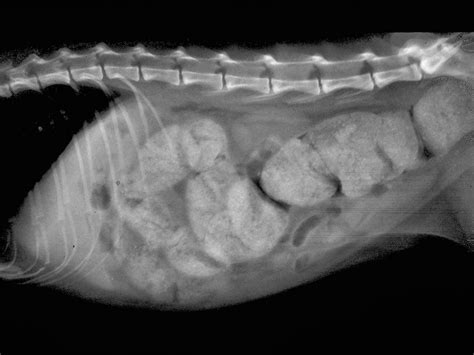

• Imaging Studies: X-rays or ultrasound can provide detailed images of the colon and help confirm the diagnosis.

• megacolon in cats xray